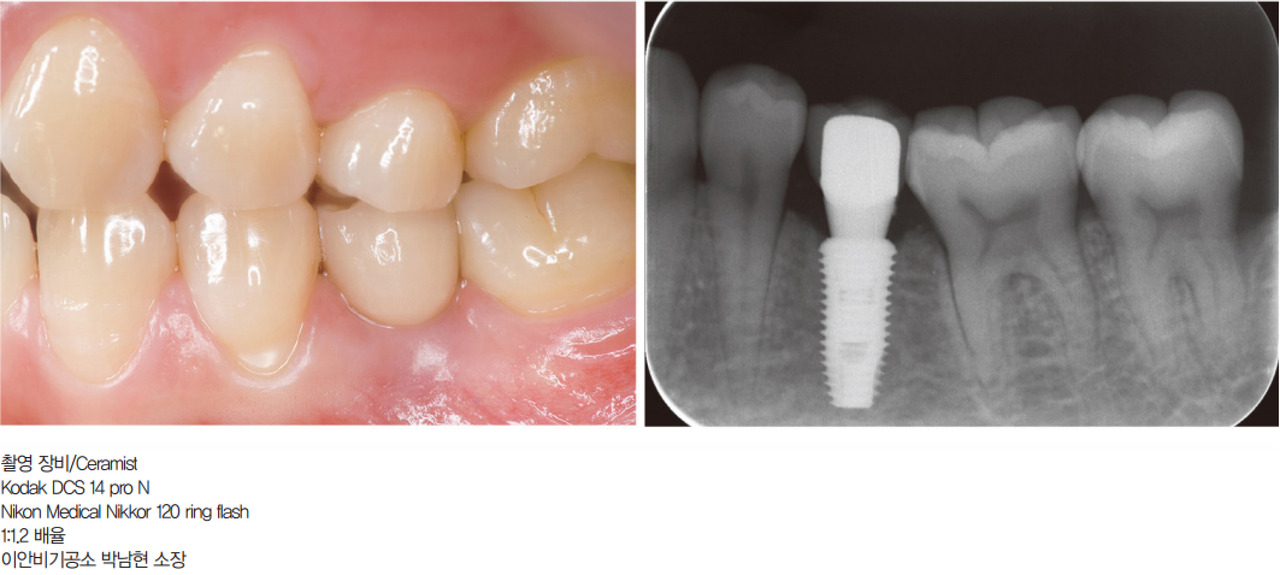

#12 zirconia 보철

이 증례처럼 D계열 색상에 노란색 수평 줄무늬가 있는 치아는 보철물 제작이 어렵다. 정확한 기저색 선택 후 shade tab과 치아를 촬영한 임 상 사진을 치과기공사에게 전달해야 한다.